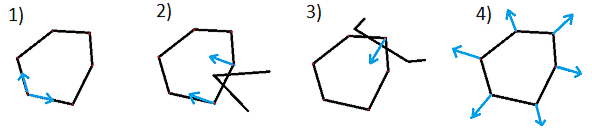

Нашу стопку срезов, полученную на предыдущем этапе, мы режем восемью плоскостями (по аналогии с разрезанием торта) и все вычисления проводим уже в пространстве плоскостей:

Если отобразить нормализованные значения интенсивностей вокселей, попавших на режущую плоскость, то получим такую картину:

Для обнаружения границ сосуда используется классический подход (edge detection by gradient) совместно с поиском пути. Схема:

Как видно из изображения, есть участки, в которых границы обнаружены неправильно. Это происходит из-за наличия кальция, что в результате приводит к обнаружению границ кальция, а не границ сосуда. Чтобы такого не происходило после первого обнаружения границ необходимо определить порог кальция (об этом дальше), а затем выполнить второе обнаружение границ, игнорируя воксели, относящиеся к кальцию. Тогда получим: